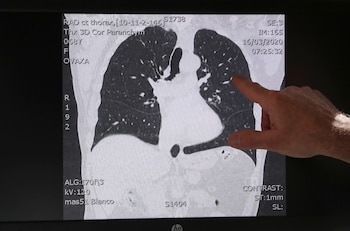

Otros modelos, como el de Alibaba, trabajan sobre imágenes de tomografías computadas: el algoritmo de IA del gigante tecnológico chino distinguió con un 96% de confiabilidad la neumonía común de la causada por el nuevo coronavirus, según un informe de Nikkei Asian Review. Y sólo demora 20 segundos.

Este desarrollo del instituto de investigación de Alibaba, Damo Academy, comenzó por entrenar el modelo de IA con datos de muestras de más de 5.000 casos confirmados. Se probó en el nuevo Hospital Qiboshan de Zhengzhou, en la provincia de Henan, que se hizo a partir del modelo del Hospital Xiaotangshan de Beijing, erigido en 2003 durante la crisis del síndrome respiratorio agudo grave (SARS), y se llevó a más de 100 instituciones médicas en las provincias de Hubei, Guangdong y Anhui.